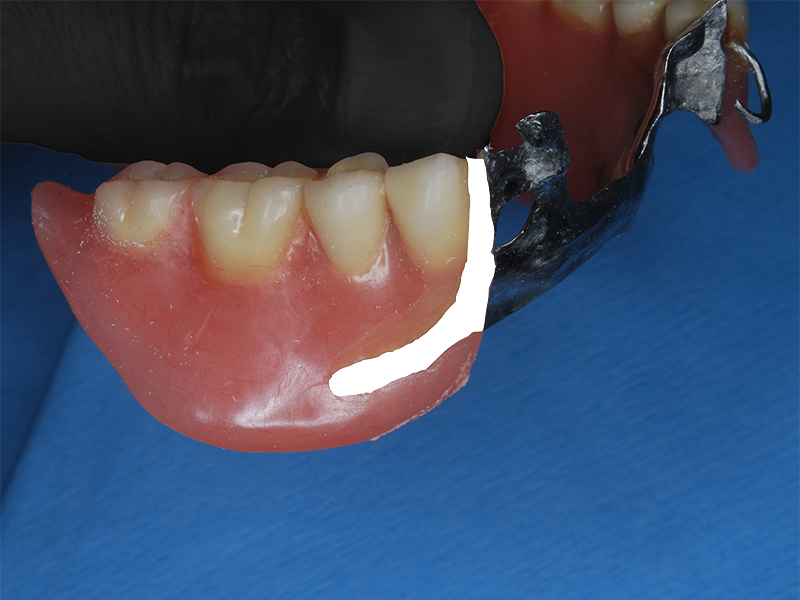

修理部分に凹みをつけ装着して型を取る

模型上で凹み部分にクラスプ新製